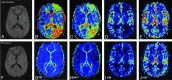

Results: Among 1850 MR imaging studies, 20 (1.08%) patients were found to have acute migrainous aura. Hypoperfusion was found in 14/20 patients (70%) with delayed rMTT and TTP, decreased rCBF, and minimal decrease in rCBV. In contrast to the typical pattern in stroke, perfusion abnormalities were not limited to a single vascular territory but extended to >1. Bilateral hypoperfusion was seen in 3/14 cases. In 11/14 cases, hypoperfusion with a posterior predominance was found. TTP and rMTT were the best maps to depict perfusion changes at visual assessment, but also rCBF maps demonstrated significant hypoperfusion in quantitative analysis. In all patients, clinical and imaging follow-up findings were negative for stroke.